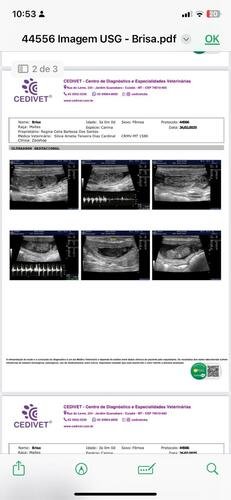

A briza, uma cachorrinha muito querida e carinhosa, de apenas 4 anos,foi encontrada na beira de uma estrada, com risco de atropelamento. Então resgatei ela e percebi que estava com muitos carrapatos, corri com ela para o veterinário para fazer exames. Os resultados dos exames acusaram uma infecção nela, precisou fazer uma ultrassom para localizar a fonte da infecção e assim foi notado que ela estava gestante de 6 filhotes, e três já estavam mortos. E se nada fosse feito os outros cachorrinhos poderiam morrer e até mesmo ela. Foi necessário uma cirurgia de emergência. Na tentativa de tirar os filhotes com vida, infelizmente não resistiram.